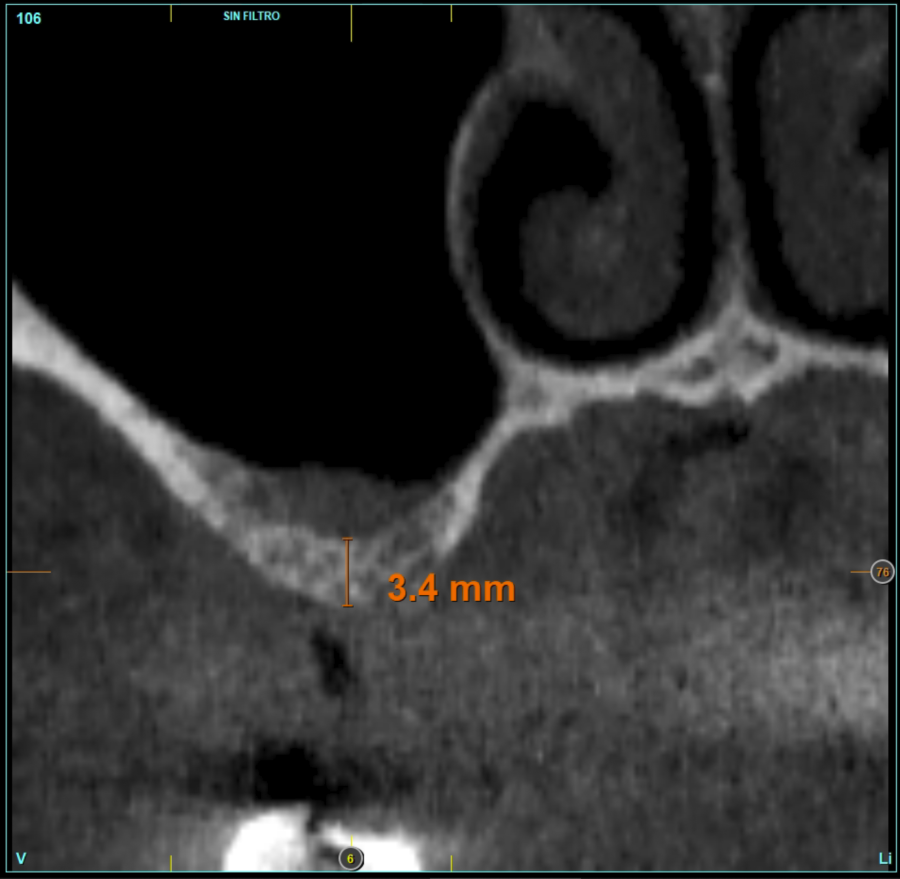

In all cases, a diagnosis was made based on study models, intraoral examination of the patient and performing a Cone-beam analysed using the specific BTI-Scan 3 software (Biotechnology Institute, Vitoria, Alava, Spain).

Patients attend subsequent check-ups performing a control Cone-Beam after 5 months (before loading the implant) and after one year of the load, performing a new measurement in these images to analyse the bone gain and the maintenance of the same. In these check-ups, data are collected on prosthetic complications or crestal bone loss in these patients, as well as possible failures.

The mean height of the residual bone volume was 3.1 mm (+/- 0.3 mm with a range of 3-4 mm). In all cases, transcrestal sinus elevation was performed, with particulate autologous bone obtained from milling the neo alveolus generation zone for implant insertion, being the average of this elevation above the apex of the implant of 2.8 mm (+/- 0.99 range 1.9 -5 mm). In the CT control scan after one year of inserting the studied implants, the bone gain achieved was maintained, no decrease in the volume gained was observed, only three cases showed a decrease of between 0.4 and 0.5 mm of the initial volume at the end (Table).

Figures 2-19 show one of the cases included in the study.